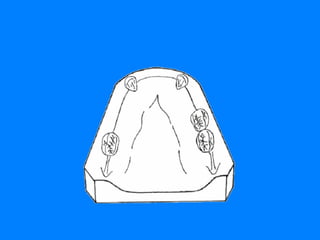

QUE SE ENTIENDE POR EFECTO DE ARCO CRUZADO ES EL EFECTO QUE SE CONSIGUE PARA LA RPR CUANDO LOS COMPONENTES DE LA MISMA UBICADOS EN UN LADO DEL  ARCO DENTAL AYUDAN A LOS COMPONENTES DEL LADO OPUESTO BUSCANDO UN MEJOR SOPORTE, ESTABILIDAD Y RETENCION. CUANDO LOS DOS LADOS DE UNA RPR SE UNEN A TRAVES DE LA LINEA MEDIA POR UN CONECTOR RIGIDO,  TODOS LOS DIENTES PILARES INVOLUCRADOS EN SU DISEÑO RECIBEN EL EFECTO DE ARCO CRUZADO. AL ENCONTRAR EN EL ARCO DENTAL DOS DIFERENTES SUPERFICIES QUE PUEDEN COLABORAR CON LAS FUNCIONES DE SOPORTE, ESTABILIDAD Y RETENCION  DE LA R.P.R. SE DEBE HABLAR DE  ARCO CRUZADO DENTAL Y MUCOSO  PARA ACLARAR A QUE FUNCION SE ESTA HACIENDO REFERENCIA

EFECTO DE ARCO CRUZADO DENTAL UNILATERAL LIMITACION 44 RESTAURACION  DENTO MUCO- SOPORTADA Hace referencia a las tres funciones, ya que los dientes pilares pueden colaborar positivamente en cada una de ellas

EFECTO DE ARCO  CRUZADO MUCOSO ESTE SE LIMITA UNICAMENTE A LA POSIBILIDAD QUE PUEDEN BRINDAR EL PALADAR Y LOS REBORDES RESIDUALES ( ARCO MAXILAR )  Y  ( ARCO MANDIBULAR ) DE COLABORAR EN LAS FUNCIONES DE SOPORTE Y ESTABILIDAD, YA QUE LA FUNCION DE RETENCION EVITANDO EL DESALOJO DE LA RESTAURACION PARCIAL REMOVIBLE ES UNA FUNCION  BASICA   DE LOS DIENTES PILARES.

CLASE I LIMITACION 14-24   DOBLE EFECTO DE ARCO CRUZADO REBORDES RESIDUALES Y PALADAR EFECTO DE ARCO CRUZADO MUCOSO CLASE I LIMITACION 34-44 DOBLE EFECTO DE ARCO  CRUZADO REBORDES RESIDUALES